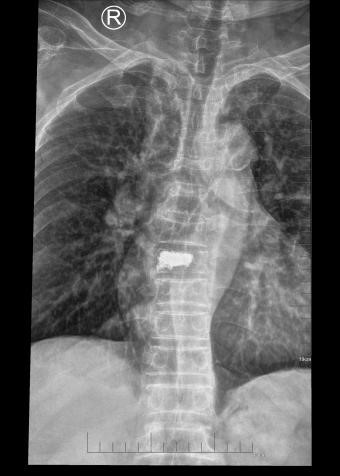

吴老太太今年86岁,同时患有心脏病、老慢支、哮喘、糖尿病等多种疾病,不久前因为并发心衰、呼衰在独墅湖医院经抢救后脱离危险。然而不巧的是,几天前自己在家只轻轻扭了一下腰,就感觉背部疼痛难忍,寝食难安。于是来到我院骨科就诊,医生怀疑是脊柱骨质疏松性骨折,安排收治住院,对病患进行磁共振检查后证实是“第8胸椎压缩性骨折”。

医生在诊断后决定行经皮椎体后突成形术(简称PKP术),需要病人在全身麻醉下俯卧位,医生在全程透视下完成手术。对于一般的患者来说不成问题,而对吴老太太而言却难以实施。首先,她的全身情况较差,心肺功能不全,基础疾病多且严重。入院时就有明显的呼吸困难,氧饱和度只有70%左右,很难耐受全身麻醉。即使勉强度过手术阶段,术后也可能要气管插管,靠呼吸机维持生命,肺部感染则难以控制。其次,如果采用局部麻醉俯卧位手术,尽管可以规避全麻的风险,但该患者根本不能承受俯卧位对心肺功能的影响。但如果不采取手术,卧床以及日夜不停的疼痛对已经遭受过心衰和呼衰的吴老太太来说是雪上加霜。

在常规办法难以实施时,独墅湖医院骨科的医生们决定另辟蹊径,挽救病患生命。常规手术主要面临两大难题:全身麻醉与俯卧位。那么如果采用局部麻醉与侧卧位呢?对!这就是解决问题的关键!局麻可以规避全麻的风险;侧卧可以避免俯卧对心肺的影响。如此,问题似乎迎刃而解了。但是,这样的改变,尤其是侧卧位完成PKP术,导致空间位置变了,手术的难度大大增加了。而且,吴老太太耳背,局麻侧卧位手术需要病人的配合,术中的沟通也是一个问题。尽管困难重重,这也是挽救老人家生命的唯一可行的办法。

在与家属充分沟通后,3月11日上午,骨科姜为民主任亲自披挂上阵,杨小海主任医师等团队成员紧密配合,一切按计划进行。然而,刚开始消毒,预料中的问题出现了:患者开始扭动身体,又无法有效沟通,如此手术将难以继续下去。好在姜主任团队早有预案:静脉适量给药镇静。在麻醉科侯永恒副主任的密切配合下,患者恢复了平静,各项生命指标平稳。姜主任凭借高超的手术技巧,仅用25分钟即高质量地完成了这例非常规手术。